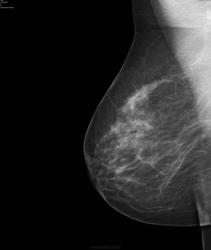

- https://radiomed.ru/sites/default/files/styles/case_slider_image/public/user/17752/bil8.jpg?itok=pL-_l44s

Слева опухолью Справа сгрукированые кальцинаты BIRADS 4 с двух сторон

Наш маммограф бы такие микрокальцинаты не нашел)) И как теперь ее будут лечить, интересно? Обе м.ж. прооперируют?